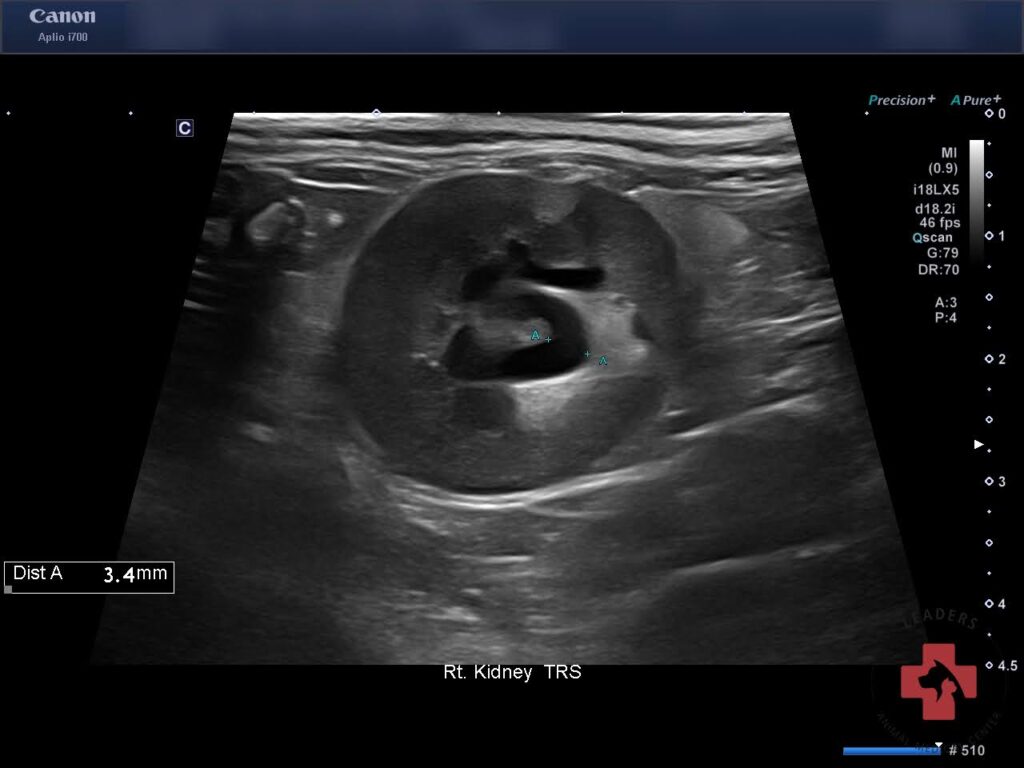

이후 실시한 본원 초음파 검사에서 양측 신장 주위 복막염 신장 피질 비후 양측 신장 신우 확장이 동반된 급성 신부전 변화가 확인되었습니다.

내원 당시 초음파검사(우측) / 출처: 동탄리더스동물의료원